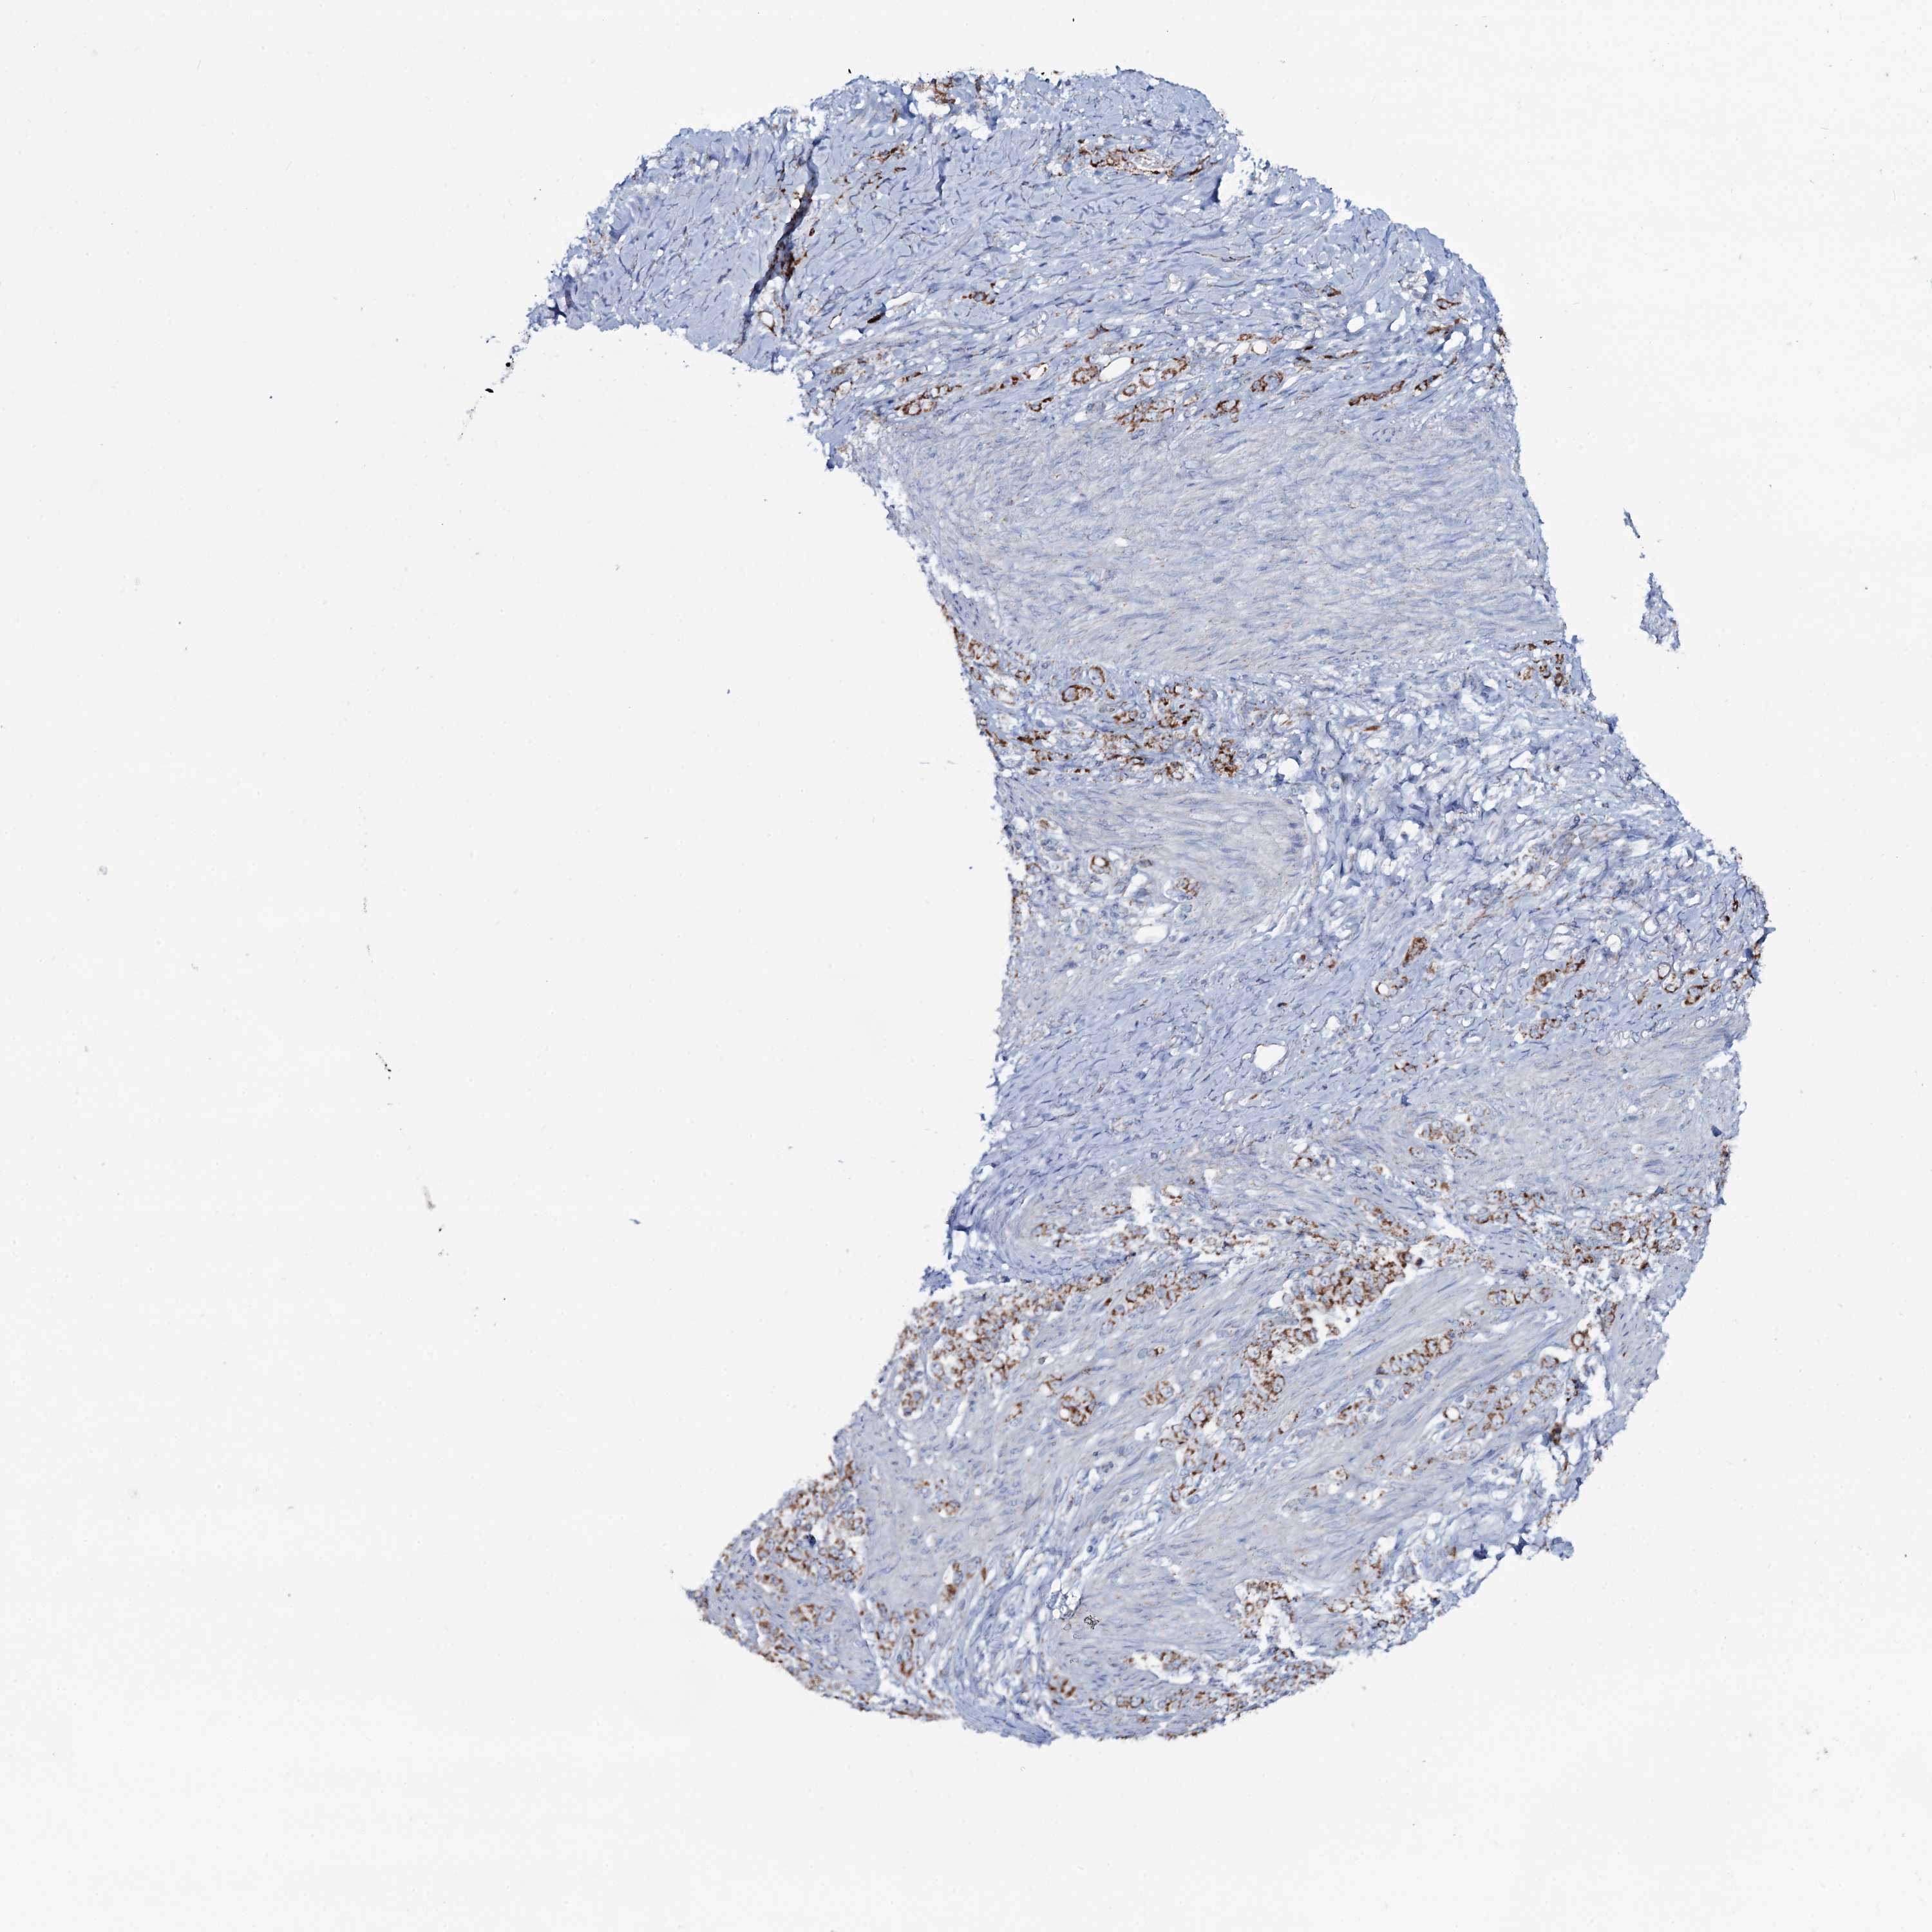

STOMACH CANCER - Protein expressioni

A mouse-over function shows sample information and annotation data. Click on an image to view it in a full screen mode. Samples can be filtered based on level of antibody staining by selecting one or several of the following categories: high, medium, low and not detected. The assay and annotation is described here.

Note that samples used for immunohistochemistry by the Human Protein Atlas do not correspond to samples in the TCGA dataset.

Antibody stainingi

Antibody staining in the annotated cell types in the current human tissue is reported as not detected, low, medium, or high, based on conventional immunohistochemistry profiling in selected tissues. This score is based on the combination of the staining intensity and fraction of stained cells.

Each image is clickable and will lead to virtual microscopy that enables deeper exploration of all samples and also displays staining intensity scores, fraction scores and subcellular localization as well as patient and tissue information for each sample.

Antibody HPA038513

Staining

High

Medium

Low

Not detected

Intensity

Strong

Moderate

Weak

Negative

Quantity

>75%

75%-25%

<25%

None

Location

Nuclear

Cytoplasmic/membranous

Cytoplasmic/membranous,nuclear

Adenocarcinoma, NOS

Adenocarcinoma, High grade